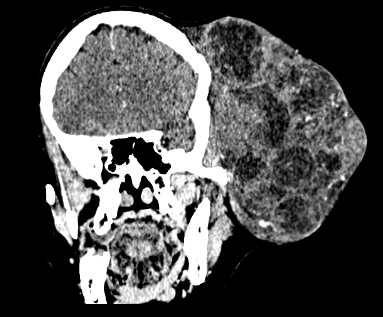

- Large, expansile mass on the left hemiface causing distortion of facial structures, including the ipsilateral eye and ear. The lesion shows two necrotic regions: one anteriorly and the other laterally.

- Soft tissue density mass, involving the superficial layers of the left hemiface, apparently originating from the cutaneous and subcutaneous tissues.

- The mass is composed of nodular material with heterogeneous attenuation. The nodules have hyperdense contours and predominantly hypodense internal contents with heterogeneous enhancement.

- Irregularity in the cranial skull with thinning and remodeling.

- There was no intracranial extension.